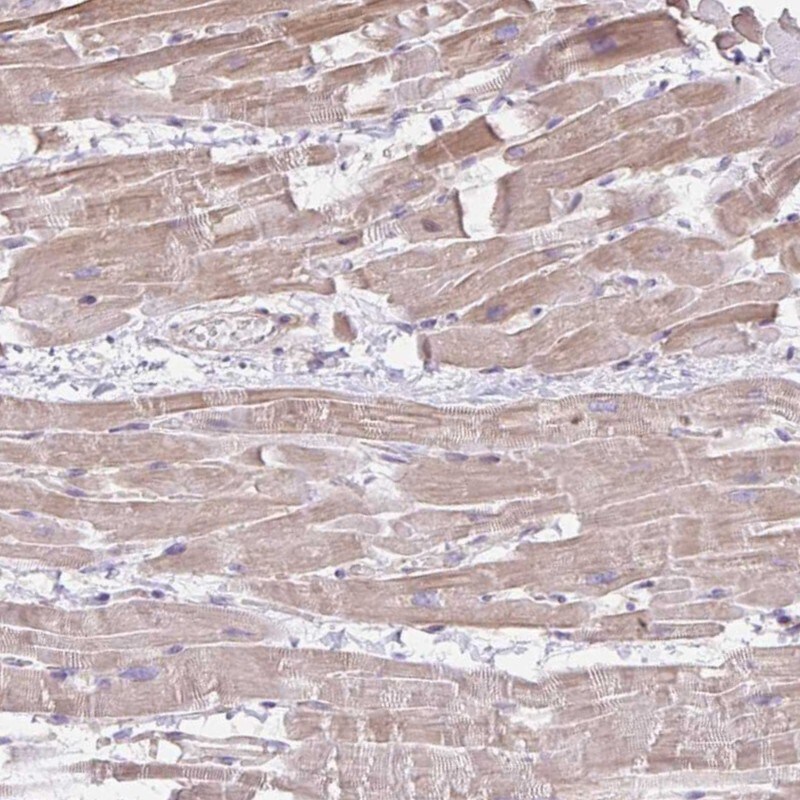

Supportive validation

- Submitted by

- Invitrogen Antibodies (provider)

- Main image

- Experimental details

- Immunohistochemical analysis of CDRT15 in human heart muscle using CDRT15 Polyclonal Antibody (Product # PA5-63218) shows moderate cytoplasmic positivity in myocytes.